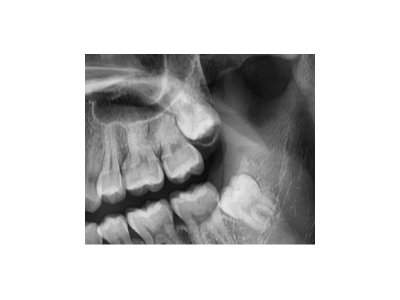

種植牙是一種常見(jiàn)的牙齒修復(fù)方式,術(shù)前準(zhǔn)備對(duì)于手術(shù)的成功和術(shù)后恢復(fù)至關(guān)重要。以下是種植牙術(shù)前的主要準(zhǔn)備工作:一、全面口腔檢查與評(píng)估口腔檢查:包括牙齒、牙齦、咬合關(guān)系、頜骨狀況等。影像學(xué)檢查:全景片(曲面…